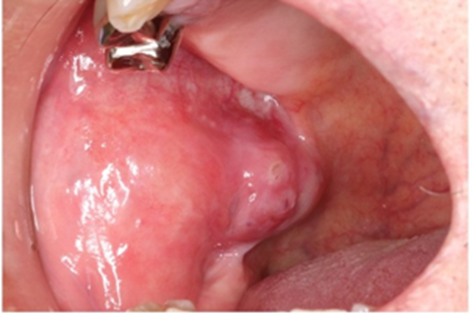

The patient was then referred to our department. General examination showed a well nourished man without cervical lymphadenopathy. An intraoral examination revealed a 26 × 22-mm firm mobile painless mass in the right buccal mucosa (Figure. 1).

Figure 1: Intraoral findings at the first visit. A painless, slightly firm elastic mass measuring 26 × 22 mm was observed in the submucosa of the right buccal region.